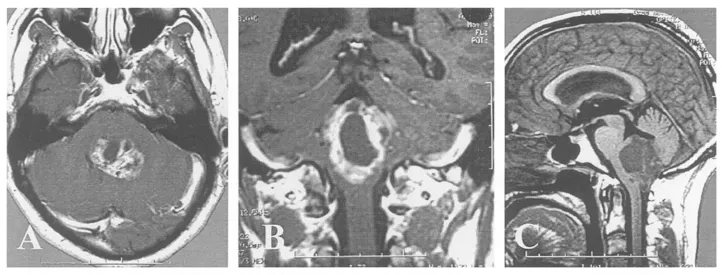

生命中枢告急!48岁男子延髓区域发现一个大型囊实性室管膜瘤,它像藤蔓一样,向上爬入第四脑室,向下钻进了椎管。

(A)硬脑膜切开后可见向下延伸至C1水平的大型肿瘤;

肿瘤已侵犯脑干,巴教授仍坚持在第四脑室底彻底切除肿瘤,以防复发,并进行细致的止血。因为研究表明,术后CT或MR影像学无肿瘤残留是长期生存的有利因素。

(D-F)术后6个月MR证实肿瘤全切。